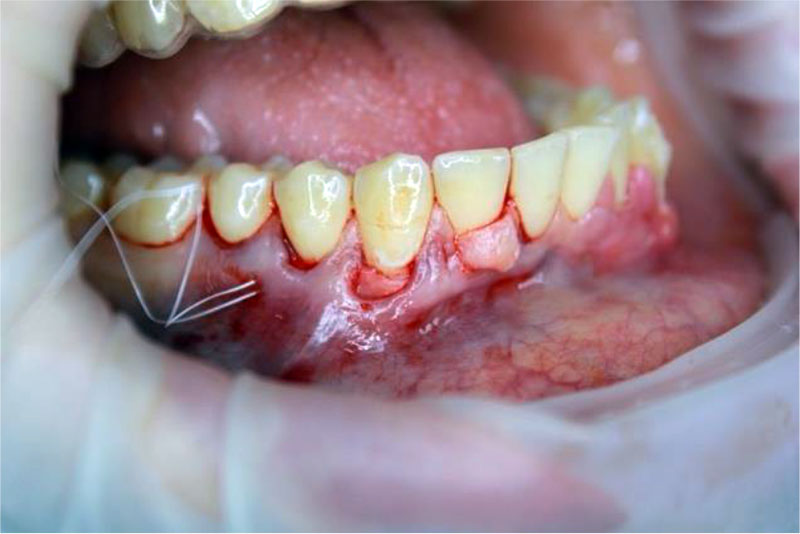

Patient A., 32 years old. Diagnosis: By 06.01 Recession of the gingiva, Miller class I. Local recession in the region of the 43 tooth (Fig. 3). The biotype of the gingiva is medium (1.0 mm), the gingival papillae are normal. Orthodontic treatment is planned. Preoperative treatment of the oral cavity was performed with 0.12% chlorhexidine solution for 1 minute. Under infiltration anesthesia Sol. Ultracaini D-S 1.7 ml performed an intrasulcular incision using a microsurgical scalpel (MANI, Japan). The exposed surfaces of the roots of the teeth were carefully processed to the height of the loss of clinical attachment in 4 stages: ultrasonic treatment, instrumental machining using Gracie Mini-Five curettes (Hu-Friedy, USA), polishing and smoothing of the tooth root surfaces using periodontal burs RA (Komet, Russia), drug treatment with the application of lincomycin hydrochloride 30 mg / ml for 2 minutes. Tunnel raspatory (Hu-Friedy, USA) exfoliated the mucous split flap and prepared the tunnel bed. A free gingival autograft was taken from the hard palate (Fig. 4) and its de-epithelization (Fig. 5), adapted in size and introduced into the tunnel bed using guides positioning sutures PTFE 5.0 (Golnit, Russia) (Fig. 6). The wound was sutured using double twisted sutures PTFE 5.0 (Golnit, Russia) (Fig. 7). Postoperative drug treatment was performed with 0.12% chlorhexidine solution. Removal of stitches after 14 days. The result after 1 month is the complete elimination of gingival recession in the area of tooth 43, but unevenness of the keratinized gingiva is observed in the area of the base of the interdental papillae (Fig. 8).

Figure 4. Elevating free gingival autograft from the hard palate.

Figure 5. Obtaining a connective tissue subepithelial autograft by deepithelialization.